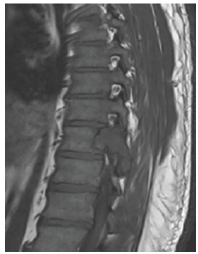

Thoracic MRI with gadolinium: heterogeneous cystic lesion (ballooning appearance) involved the posterior elements (right lamina, pedicle, facet joint) of T, narrowing of the spinal canal

With cord compression also noted (Figure 1- 3)

Figure 1:T1 MRI.